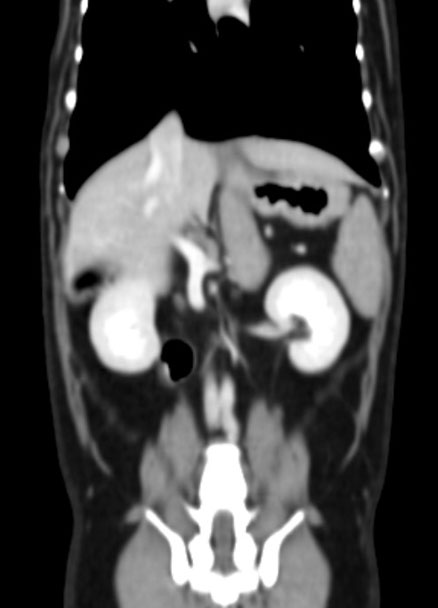

CT (Computed Tomography, 전산화 단층촬영) 검사는 X-ray를 이용해 반려동물의 몸을 여러 각도에서 촬영하고, 이를 컴퓨터로 합성하여 단면 이미지(슬라이스)를 만들어내는 정밀 진단 장비입니다.

사람 병원에서도 널리 사용하는 기술로, 뼈, 장기, 혈관, 종양 등 몸속 구조를 3차원(3D)으로 시각화할 수 있습니다.

| 복부 | 간, 비장, 신장, 위장관 종양 및 결석, 부신, 림프절 등 |

혈관 조영(Angio CT)을 통한 혈관 이상 진단